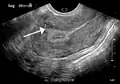

A very large (9 cm) fibroid of the uterus which is causing pelvic congestion syndrome as seen on ultrasound